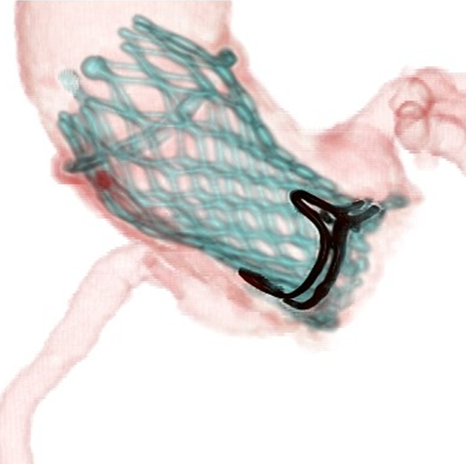

提供:エドワーズライフサイエンス(株)・メドトロニック(株)

いくつかの方法がありますが、95%以上は、足の付け根(ソケイ部)の大腿動脈からカテーテル(医療用のチューブ・管)を挿入して、大血管を通じて、大動脈弁の中に人工弁を留置する方法です。